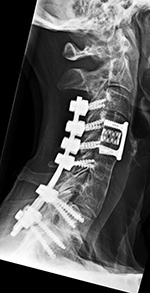

There is a hollow disk cage at C4-5 with bone chips in the cage. Posterior spinal fusion is present with lateral mass screws from C3-6 bilaterally and Pedicle screws bilaterally at T1-2 with rods running on each side from C3-T2. An anterior plate and screws is at C4-5. A laminectomy is present bilaterally through much of the cervical spine. |